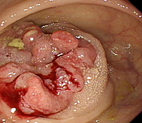

如果沒有特殊原因,所有已知、或懷疑大腸癌的患者都應該接受大腸鏡檢查。大腸鏡可以確認腫瘤性質、取得組織切片、評估嚴重度、並幫助手術前的定位,是最重要且關鍵的檢查(圖二)。診斷確定後,還需要電腦斷層檢查或其他必要的檢查,以判斷是否有鄰近器官侵犯及轉移性腫瘤。

圖二 圖中粉紅色不規則區域為環繞大腸腔的進行性大腸癌,可見到腫瘤已幾乎完全堵塞了腸管,而且不斷地有鮮血滲出。